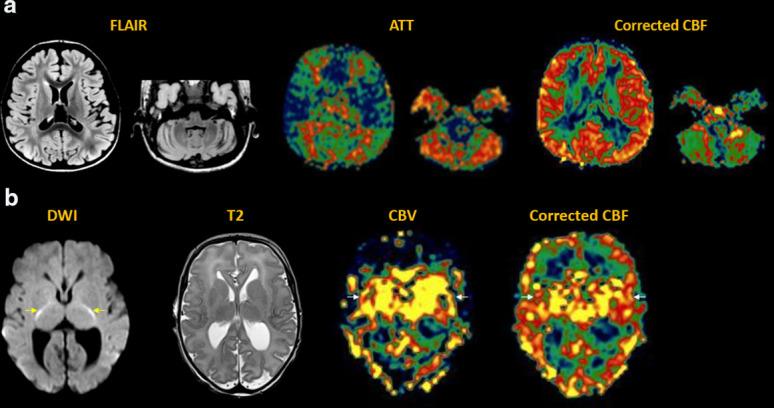

Arterial spin labeling (ASL) is a powerful noncontrast MRI technique for evaluation of cerebral blood flow (CBF). A key parameter in single-delay ASL is the choice of postlabel delay (PLD), which refers to the timing between the labeling of arterial free water and measurement of flow into the brain. Multidelay ASL (MDASL) utilizes several PLDs to improve the accuracy of CBF calculations using arterial transit time (ATT) correction. This approach is particularly helpful in situations where ATT is unknown, including young subjects and slow-flow conditions. In this article, we discuss the technical considerations for MDASL, including labeling techniques, quantitative metrics, and technical artefacts. We then provide a practical summary of key clinical applications with real-life imaging examples in the pediatric brain, including stroke, vasculopathy, hypoxic-ischemic injury, epilepsy, migraine, tumor, infection, and metabolic disease.

动脉自旋标记 (ASL) 是一种强大的非对比 MRI 技术,用于评估脑血流 (CBF)。单延迟 ASL 的一个关键参数是后标记延迟 (PLD) 的选择,它是指动脉游离水标记与脑内血流测量之间的时间间隔。多延迟 ASL (MDASL) 使用多个 PLD 利用动脉通过时间 (ATT) 校正来提高 CBF 计算的准确性。这种方法在 ATT 未知的情况下特别有帮助,包括年轻受试者和低流速情况。本文讨论了 MDASL 的技术注意事项,包括标记技术、定量指标和技术伪影。然后,我们提供了一个实用的总结,介绍了儿科大脑中的关键临床应用,包括中风、血管病变、缺氧缺血性损伤、癫痫、偏头痛、肿瘤、感染和代谢性疾病,并提供了真实的成像示例。